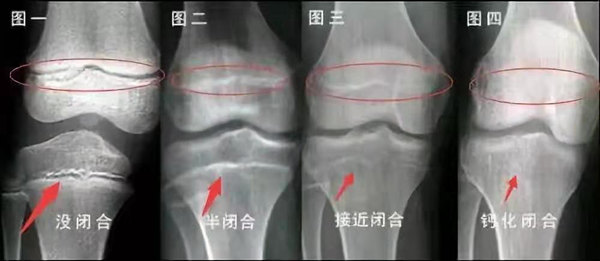

未成年時隨著年齡的增加骺軟骨端不斷骨化,骨骼就不斷增長。當(dāng)骨骺線完全閉合時骨骼就停止生長,個子也就不再增長了。一般骨骺端完全閉合的年齡是18~20歲左右。

青少年一般什么時候骨骺閉合?

一般女孩是在16歲,男孩是在18歲。

一般來說,女孩的骨齡超過14歲,男孩的骨齡超過16歲,這時其骨骺線已接近閉合,基本沒有長高的機會了。

因此,越早了解骨骺線閉合情況,越早干預(yù),孩子長高的可能性越大。